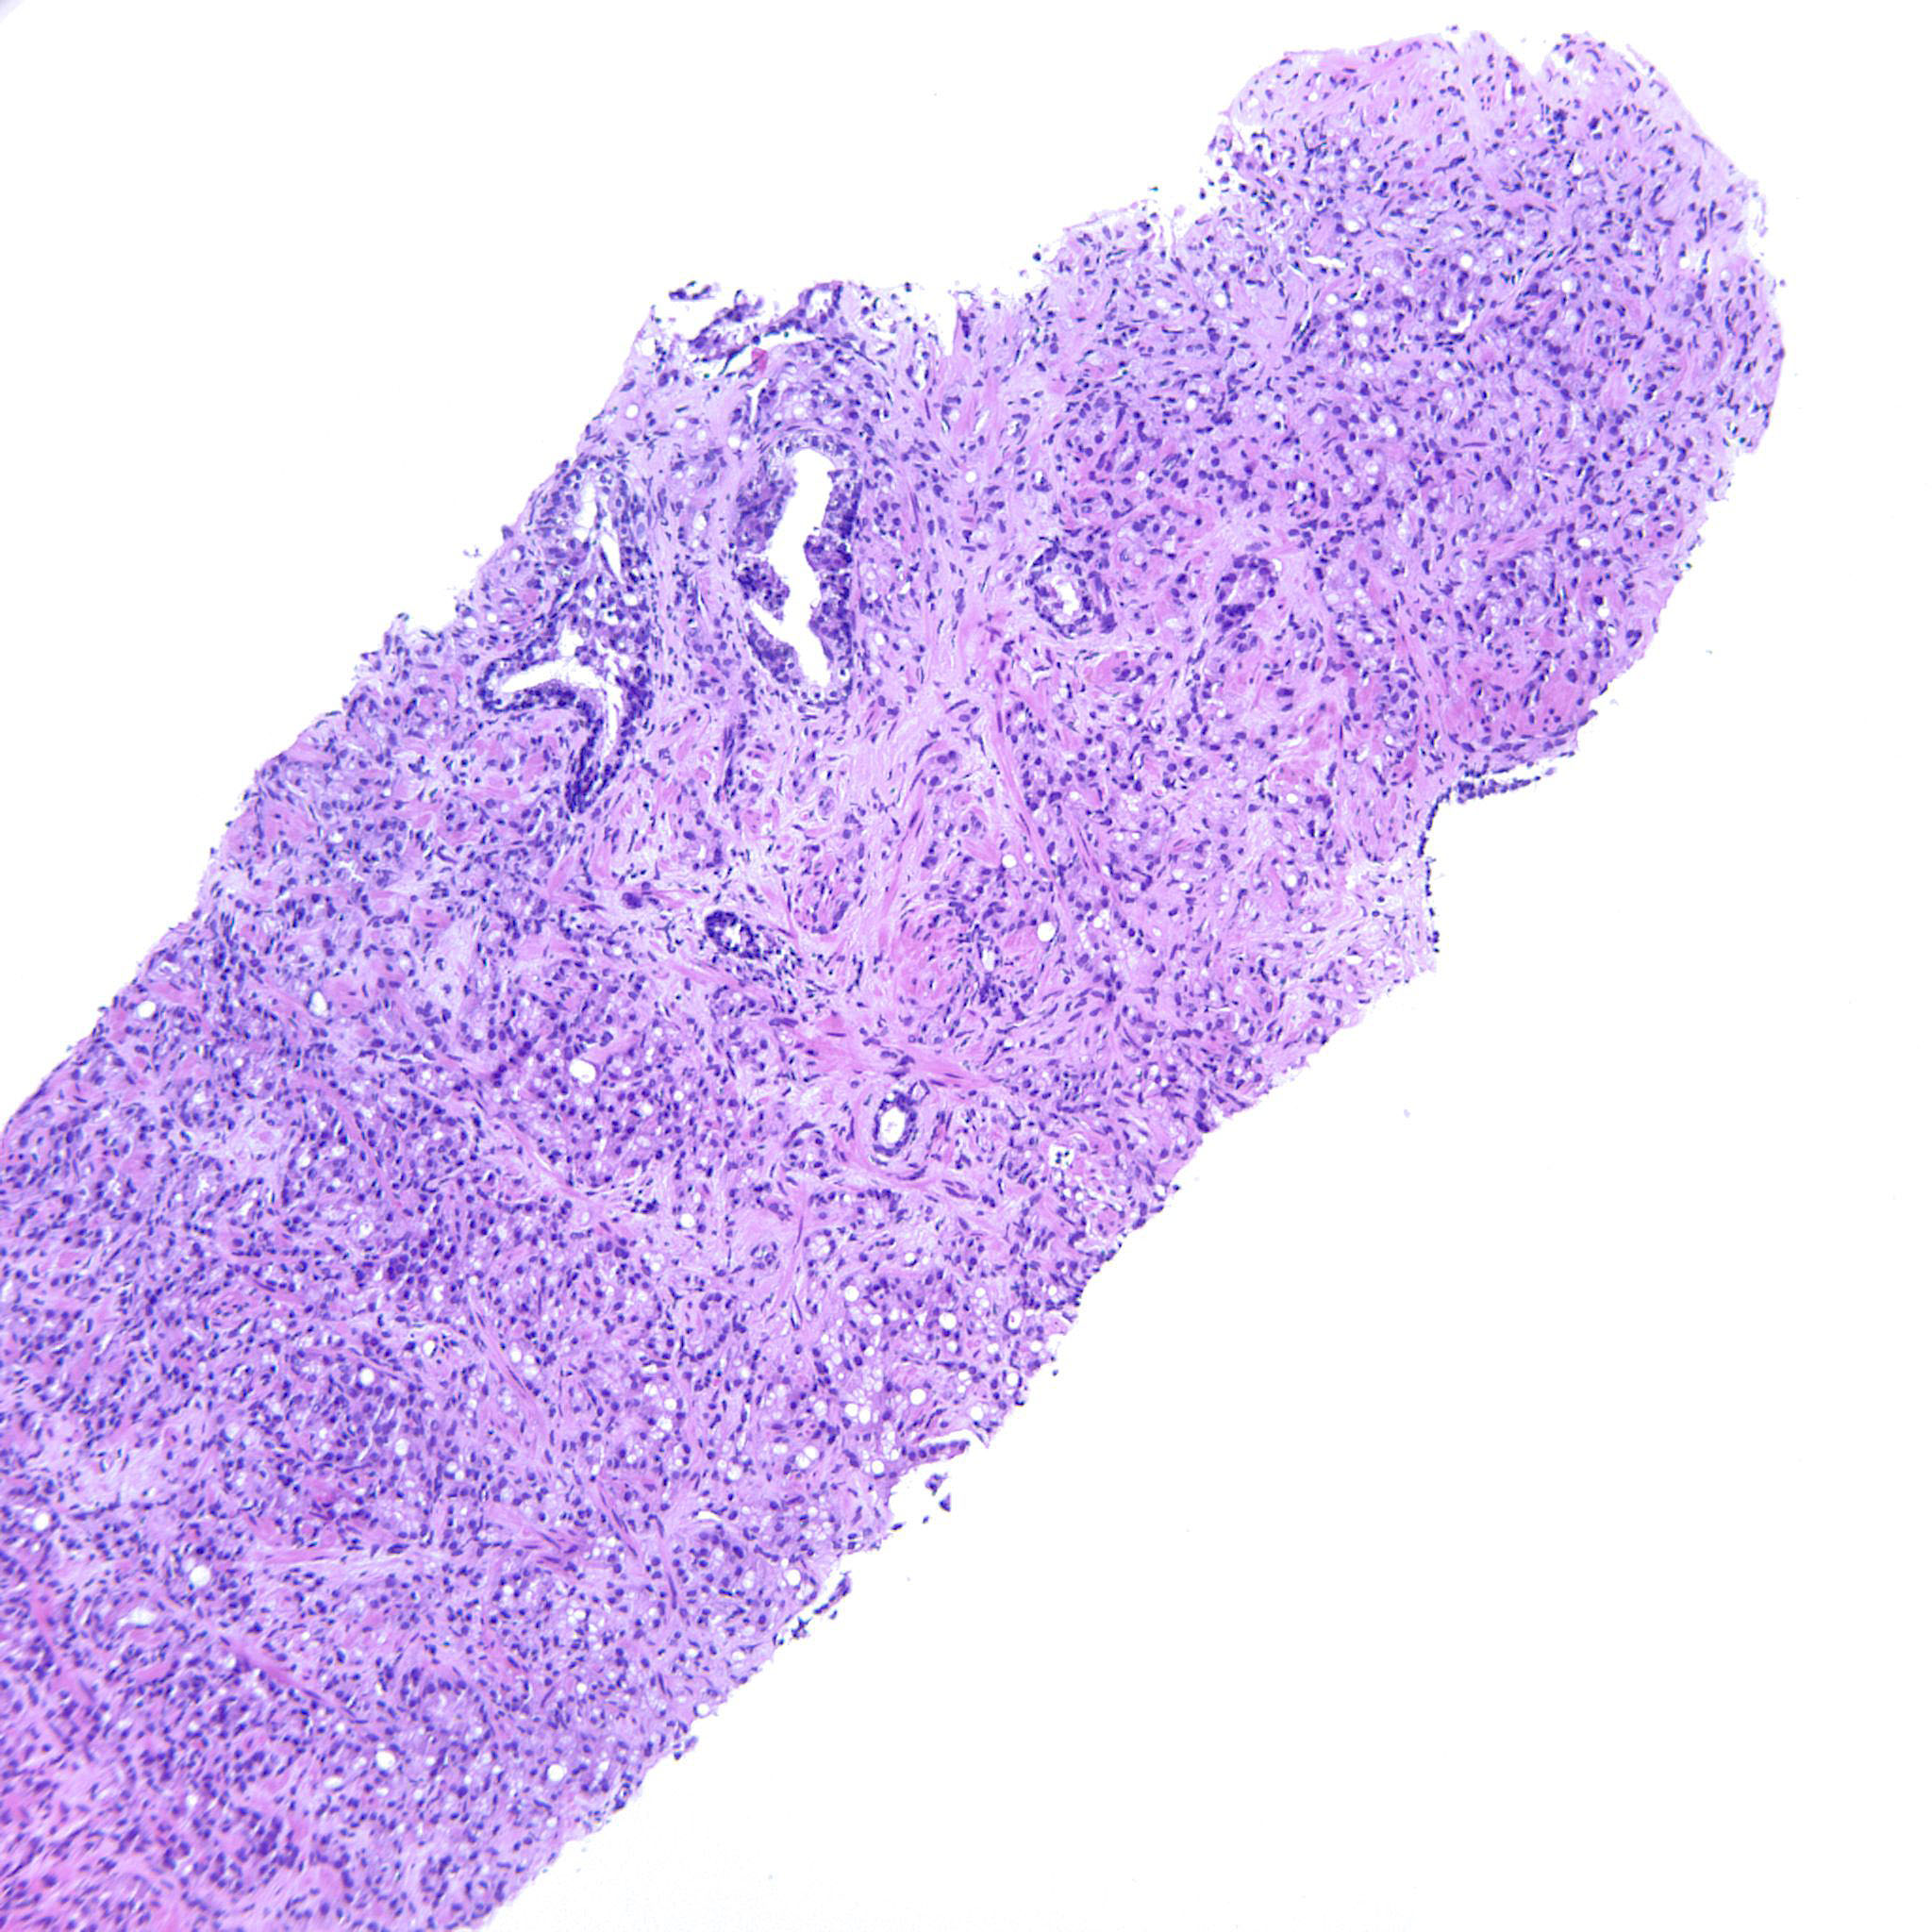

Prostate cancer grading

Case ID: 744